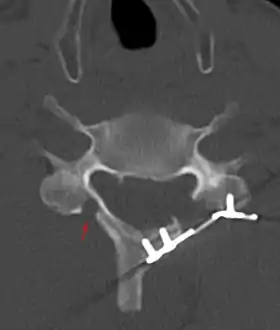

![]() CT scan of Laminoplasty of cervical vertebra | |